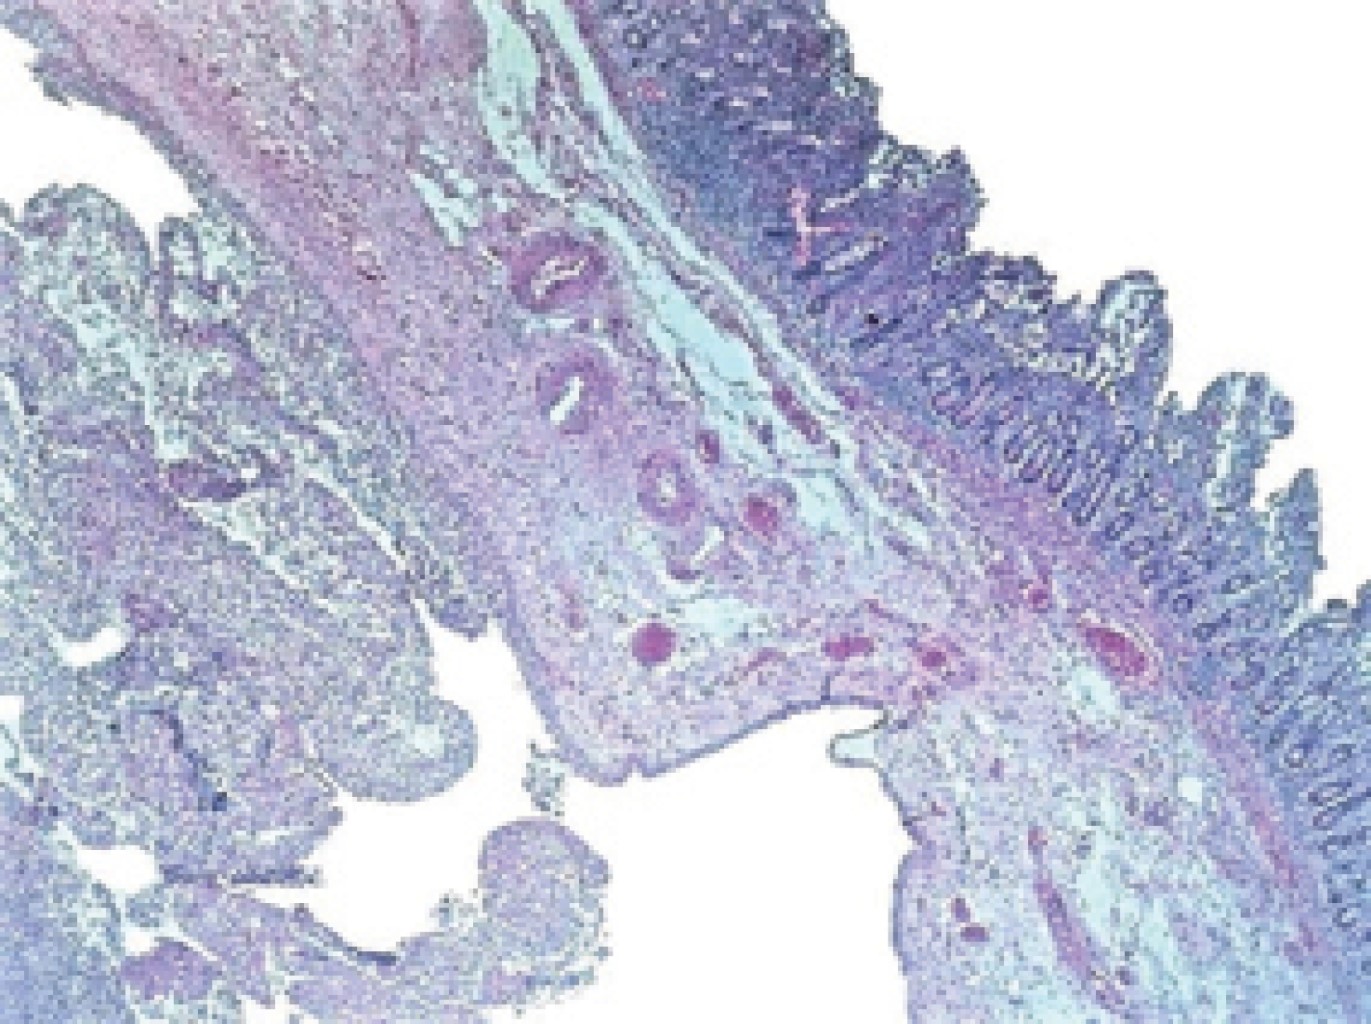

The histopathological report corroborated the clinical diagnosis, showing a thin wall with congestion and perforated diverticular disease leading to acute peritonitis (Figures 3, 4, 5, 6 and 7).

Figure 1

Figure 2

Figure 3

Figure 4

Figure 5

Figure 6

Figure 7